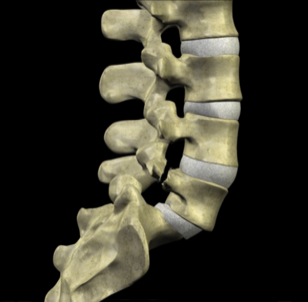

To understand how both mechanisms cause slippage, it is important to understand the anatomy of the vertebral motion segment. Each level of your spine functions as a three-joint complex. There are two facet joints in the back and a large disc that acts as a joint in front. This tripod creates great stability, supports the weight above each level and provides support for movement in all directions. As long as the disc remains healthy, it can withstand these forces for many years without any symptoms.

The pars functions as a bony hook and when fractured the posterior support for the vertebrae is broken. It can cause a forward slippage with time.